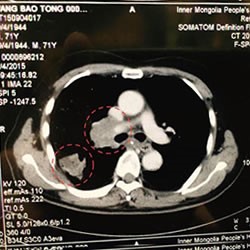

肺癌、 纵隔镜 淋巴结转移(71岁男性)

来院

(抗PD-1抗体)病例

肺癌、 纵隔镜 淋巴结转移(71岁男性)

治疗前摄影图CT (治疗前:CT)

开始治疗后70日后(2个月半)(治疗 70天后)

中国来的患者

来院 PD-1免疫抗癌剂

(抗 PD-1 抗癌剂) 案例

*肺癌, 纵隔镜 淋巴结转移(71 岁男性)

来自中国的一名患者. 1疗程 5回 PD-1免疫抗癌剂(抗PD-1抗癌剂)

并用 免疫疗法NK・T细胞疗法 肿瘤减少了一半以上.

目前.以彻底消除肿瘤为目标.进行第2疗程的治疗.